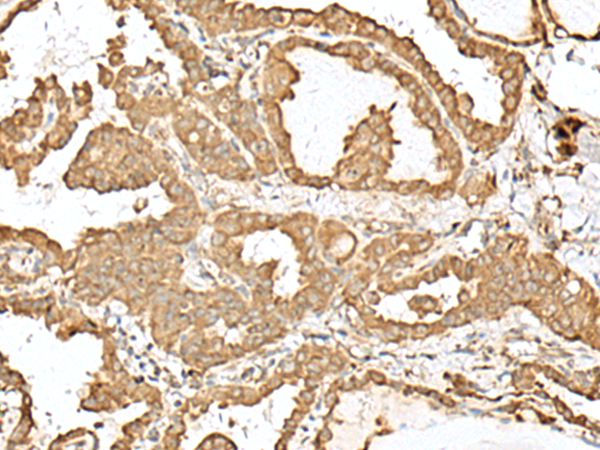

分类: 科研抗体货号: P09798别名: ESG; ESG1; GRG1应用: WB,IHC反应种属: Human, Mouse